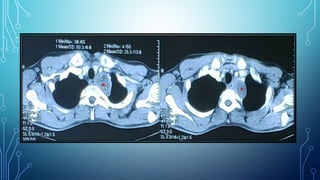

A Pancoast tumor is a rare form of lung cancerThis type of tumor is located at the very top apex of the right or left lung. Im going to do everything in my power just to be here for them and to create the memories I didnt get to create with my mother Read Debbies story. Hi Diana I so hope that you will answer this.

Less than 2 of patients with Pancoast tumor have a normal chest x-ray so a simple investigation can allow for timely diagnosis -- and appropriate treatment-- given clinician. He told me that I had a large tumor at the top of my right lung called an apical. 34 year old female.